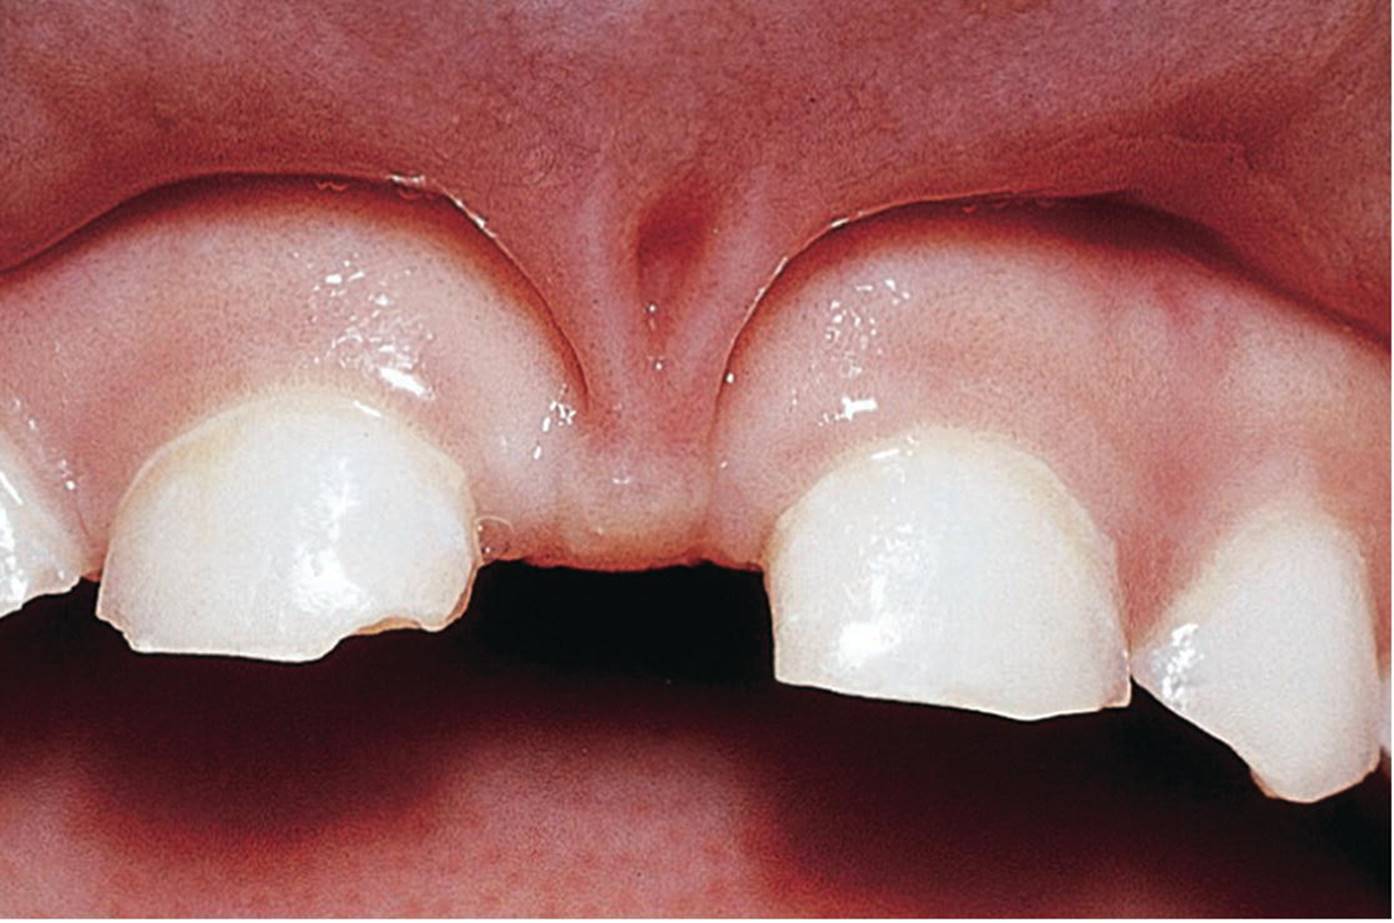

Occasionally, the frenulum labii superioris has a broad attachment to the upper lip with a thick fibrous string attaching the frenulum to the papilla between the incisors. This strong fibrous part of the frenulum can cause “blanching” of the papilla when forward tension is applied to the upper lip. A bony cleft or fissure can often be found between the central incisors in combination with an extensive diastema. In general, no treatment is necessary as most of these “abnormal” frenula and the diastema will normalize and disappear at the time of the eruption of the permanent incisors and canines. However, if there is no spontaneous closure of the diastema, surgical intervention is recommended. In cases with very fibrous and extensive frenulum labii superioris, causing deep bony defects between permanent central incisors, the surgical treatment may be performed before the eruption of the permanent central incisors (Figure 15.30).